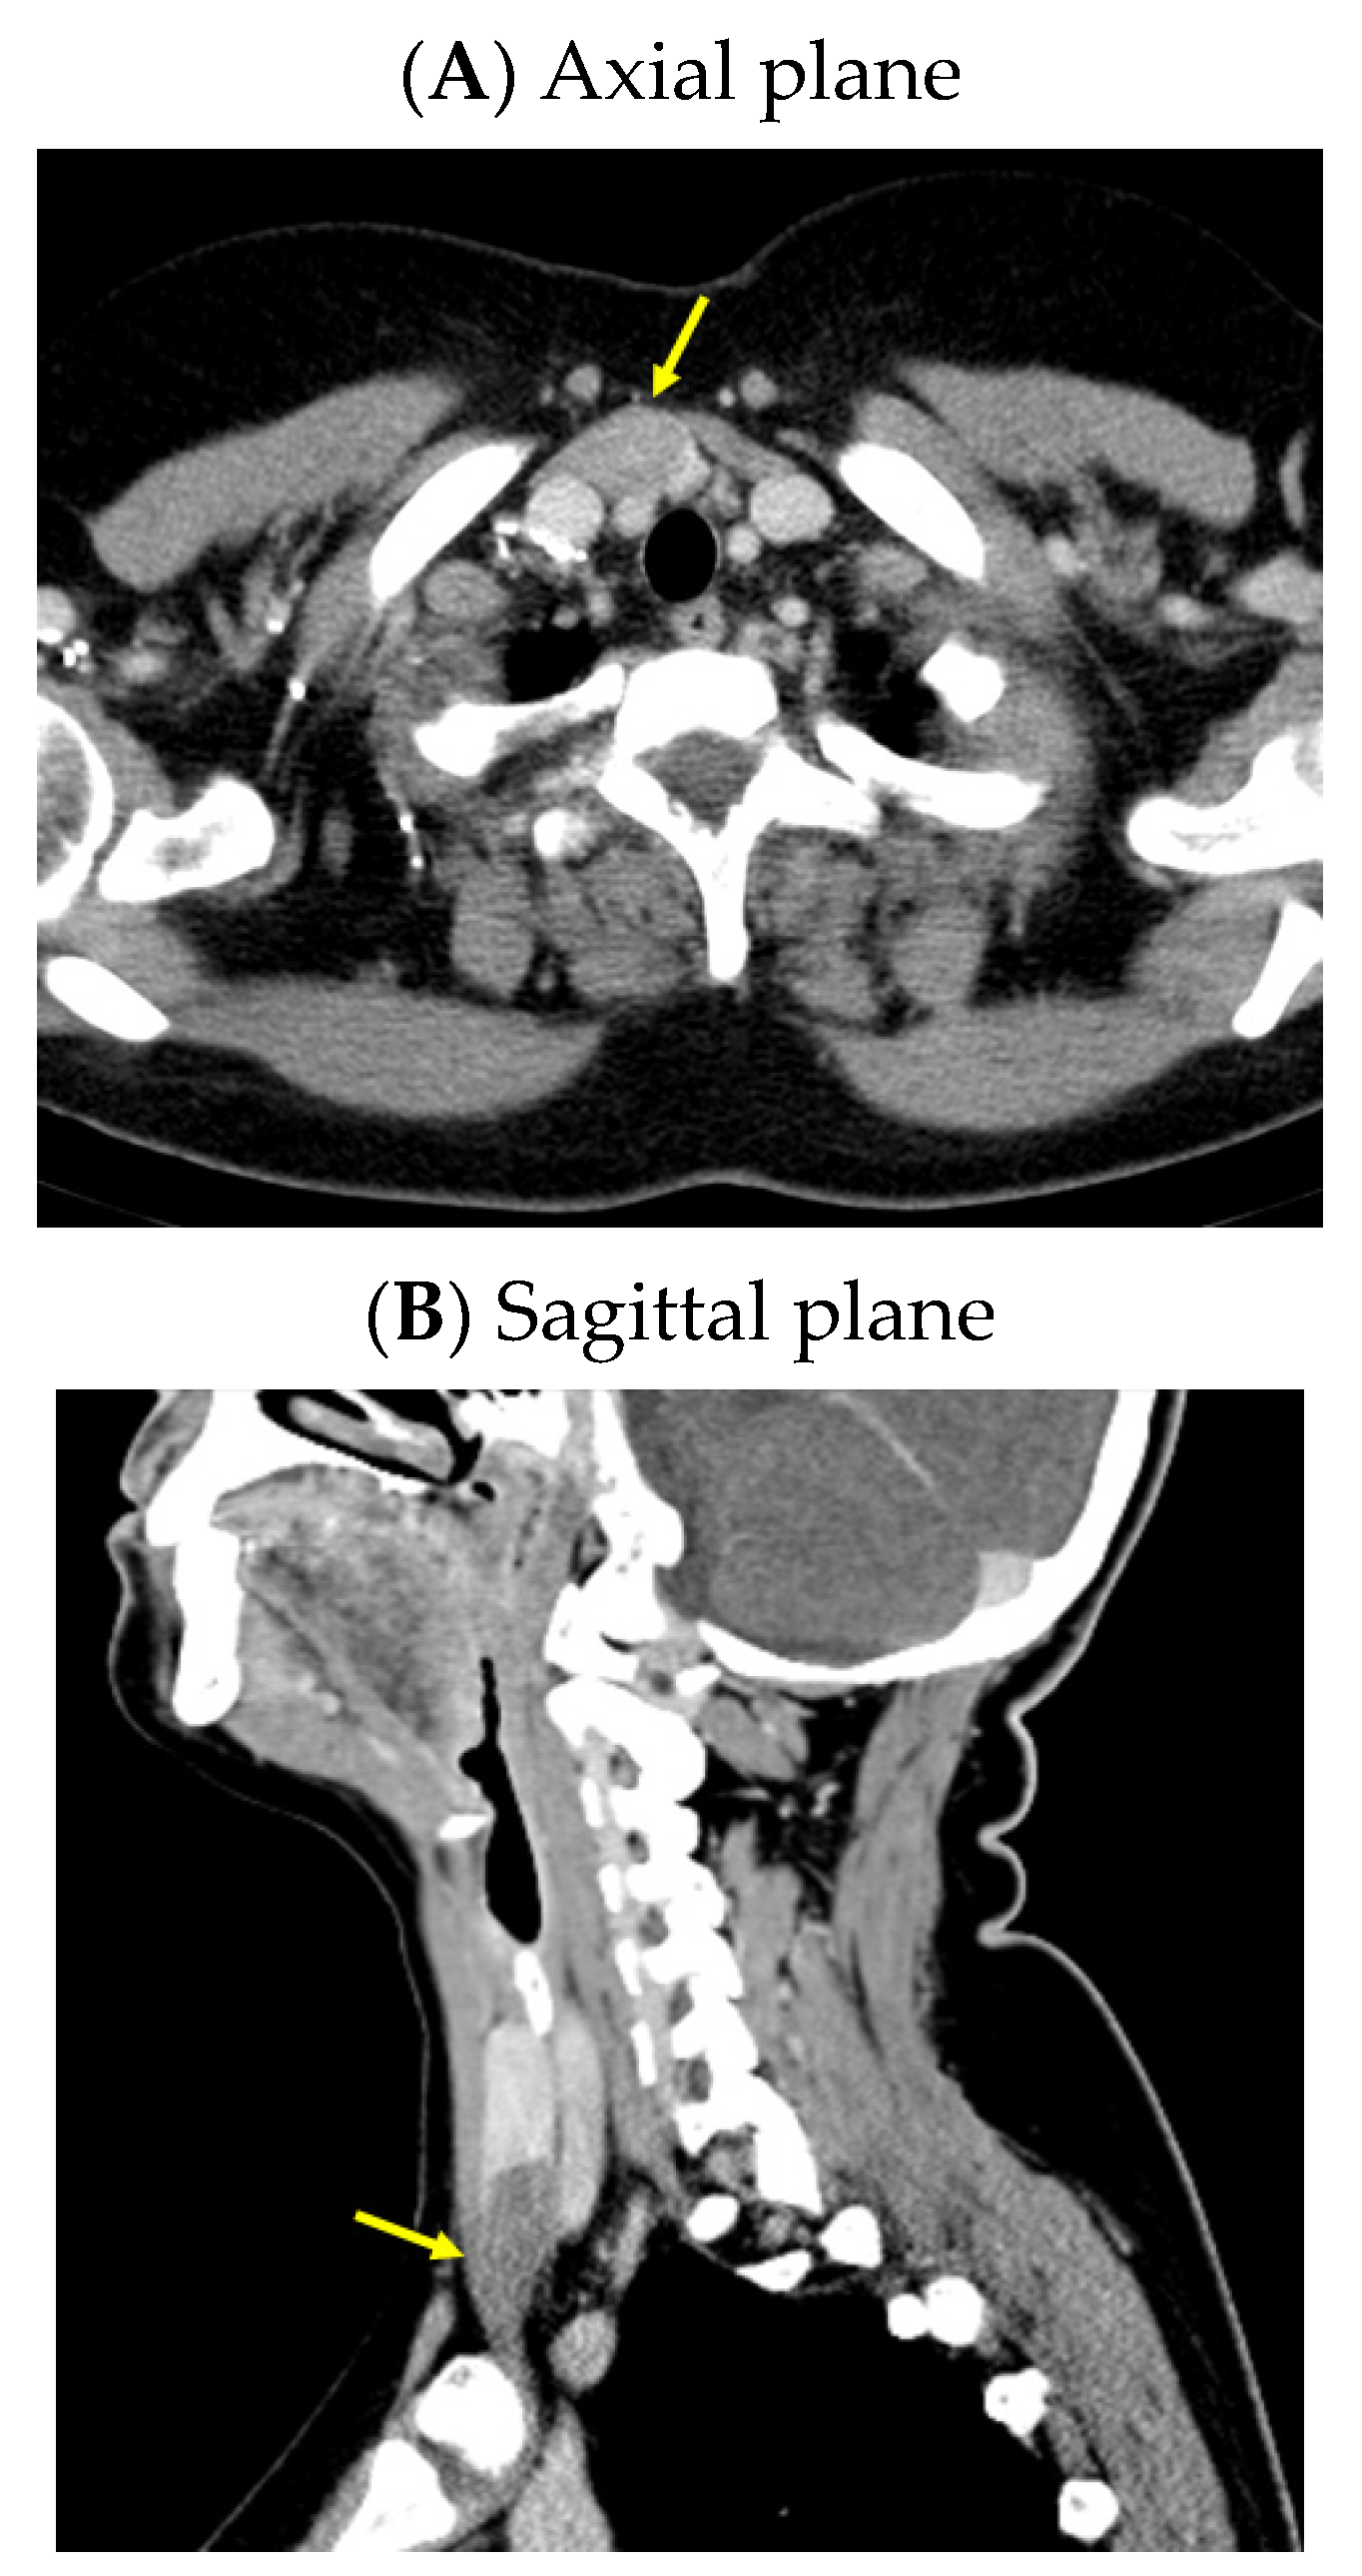

An anterior neck ultrasound revealed that posterior and inferior to the right thyroid lobe, a hypoechoic, inhomogeneous, and highly vascularized nodule of 3.98 by 1.13 by 2.53 cm was found, suggestive of a right inferior parathyroid tumor. Furthermore, a right thyroid lobe of 1.70 by 1.36 by 5.25 cm and a left thyroid lobe of 1.60 by 1.12 by 5.11 cm with a hypoechoic, inhomogeneous, micronodular pattern and normal vascularization were identified; the isthmus was of 0.35 cm with a hypoechoic, inhomogeneous nodule of 1 by 0.50 by 0.97 cm. A computed tomography (CT) scan confirmed the single parathyroid tumor (a hypodense nodule of 2.48 by 1.80 by 3.69 cm) (Figure 1).

Figure 1.

Intravenous contrast CT scan: right inferior parathyroid tumor (yellow arrow) displayed as a hypodense nodule of 3.98 by 1.13 by 2.53 cm.

A CT scan confirmed the rib tumor mass (highly suggestive of a brown tumor) located in the middle and posterior part of the left sixth rib that caused median cortical destruction (of 3.09 by 5.13 cm in the axial plane, 2.53 by 3.31 cm in the coronal plane reconstruction, and 6.11 by 3.46 cm in the sagittal plane reconstruction) (Figure 5).

Figure 5.

Intravenous contrast CT: a tumor mass located in the middle and posterior part of the left sixth rib, with median cortical destruction of 2.53 by 3.31 cm, suggestive of a brown tumor (yellow arrow).

A pelvis CT scan confirmed the osteolytic lesions of the ischium and of the left coxal bone adjacent to the acetabular fossa, measuring 1.97 by 3.29 cm and 1.14 by 1.71 cm, respectively (brown tumors) (Figure 6).

Figure 6.

Pelvis CT scans showing other brown tumors: (A) osteolytic lesion of the left coxal bone adjacent to the acetabular fossa of 1.14 by 1.71 cm (axial plane); (B) osteolytic lesion of the left ischium of 1.97 by 3.29 cm (axial plane).